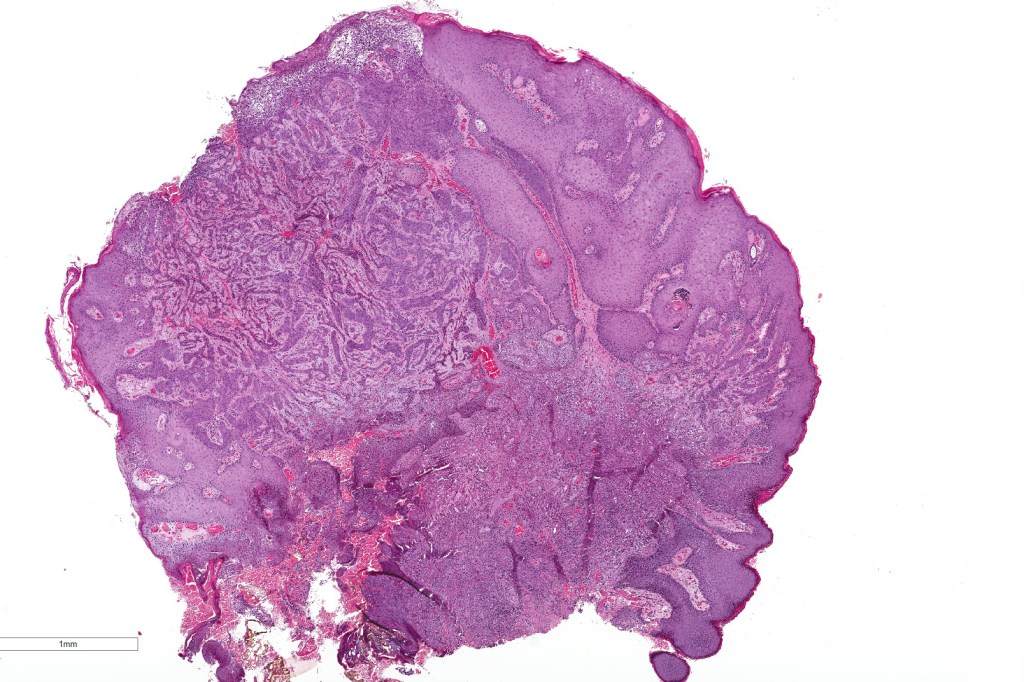

Histological features

•In situ (malignant hidroacanthoma simplex)

•Continuity/origin from epidermis (arises from the acrosyringium, distinguishes this tumor from hidradenocarcinoma)

•Pushing or infiltrating deep margin

•Broad anastomosing epithelial trabeculae